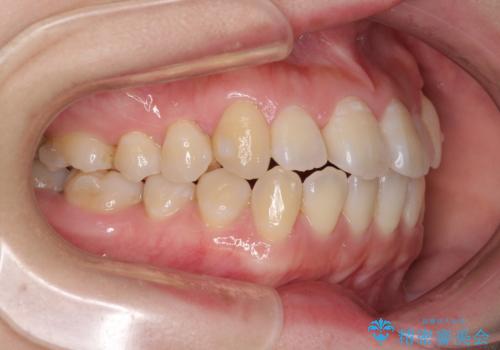

口元の突出感を改善 インビザラインによる非抜歯矯正

- 前歯がデコボコした上に口元が閉じにくいことを気にして来院された患者様です。

IPR(歯と歯の間を削る)と側方拡大では口の閉じにくさは改善できそうになく、一方で抜歯矯正を行うほどの突出感は認められませんでした。

親知らずを全て抜去し、歯列全体を後方に移動させることで口元の閉じにくさいを改善していくこととしました。

インビザラインでの歯列全体の後方移動は時間がかかりますが、しっかりと装着時間を守っていただいたので、スッキリとした口元に仕上げることができました。